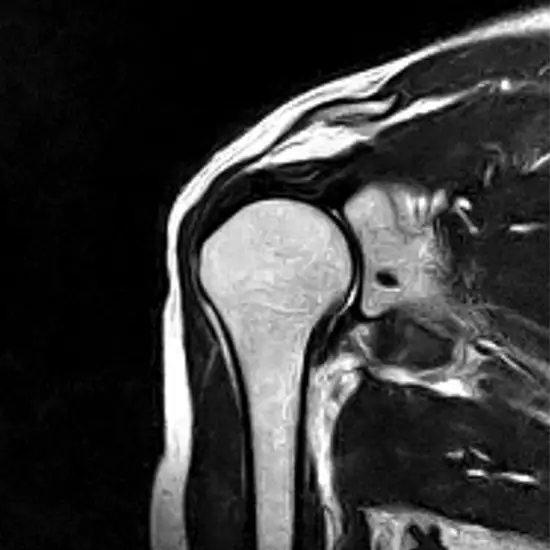

An MRI shoulder scan allows medical personnel to see the shoulder's blood arteries, bones, and soft tissues up close.